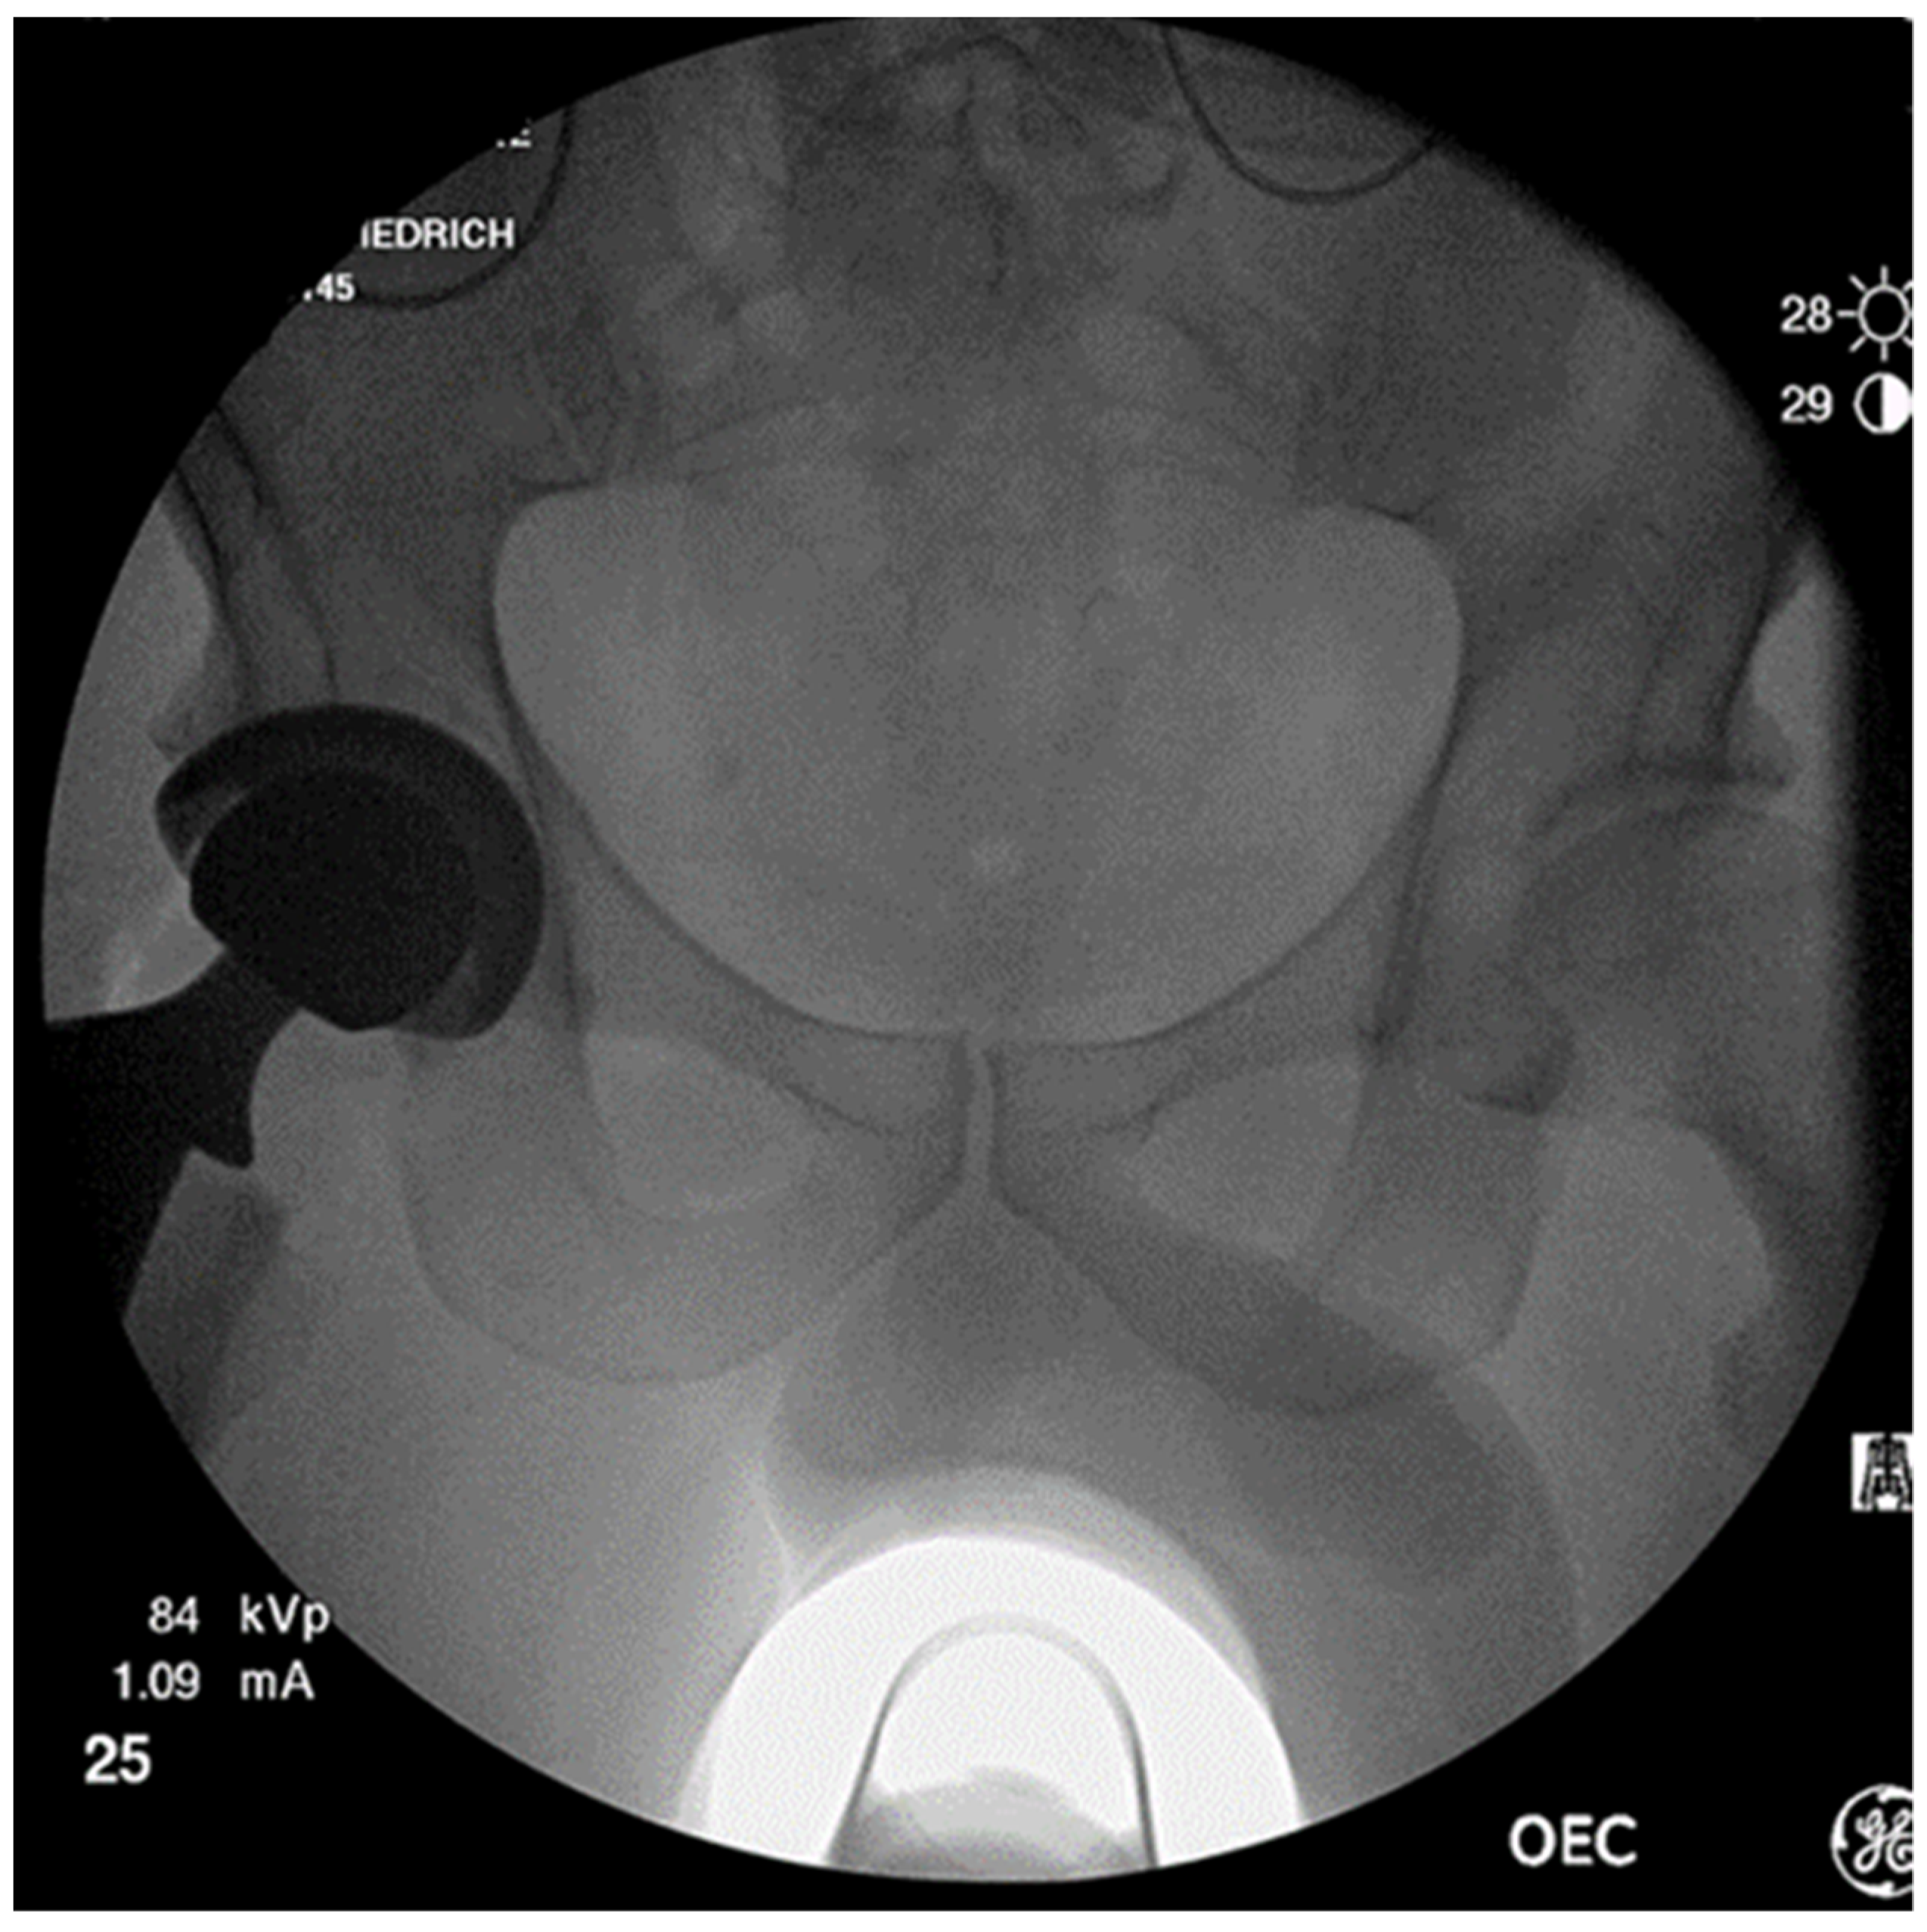

2.2. Positioning with Intraoperative C-Arm Imaging

2.2.1. C-Arm Imaging without Additional Devices

3.2. Challenges in Intraoperative Fluoroscopy and How to Address Them

3.2.3. Fluoroscopy without Additional Applications